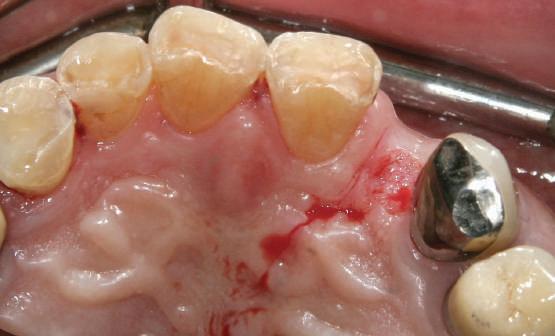

Reprepararea intraorală a bonturilor Acest pacient prezenta dentiţia maxilară compromisă, refuzând proteza mobilizabilă. Prin abordarea în etape, se menţin o parte din bonturile dentare naturale; s-a observat recesie în momentul amprentării pentru cel de-al doilea grup de implanturi.

Fig. 1 prezintă pacientul după inserarea primului set de bonturi implantare individualizate; dinţii naturali adiacenţi

sunt încă prezenţi pentru a susţine puntea provizorie.

Şapte luni mai târziu (fig. 2), acele bonturi individualizate din prima etapă au manifestat semne de recesie de 1-3mm. Atitudine: S-a decis reprepararea intraorală a tuturor bonturilor (fig. 3), astfel încât toate marginile bonturilor să fie la nivelul sau sub marginea gingivală (de notat că 1.1. şi 2.1. au fost submersaţi ulterior pentru a avea sprijin implantar deplin).

Deşi reprepararea a îmbunătăţit marcat estetica finală, a necesitat aplicarea şnurului de retracţie, amprente noi şi turnări noi.

Cazul (1): Reprepararea intraorală a bonturilor Figurile

1. Aspect după inserarea primului set de bonturi implantare individualizate.

2. După 7 luni, bonturile individualizate din prima etapă au prezentat recesie de 1-3mm.

3. Bonturile repreparate intraoral.